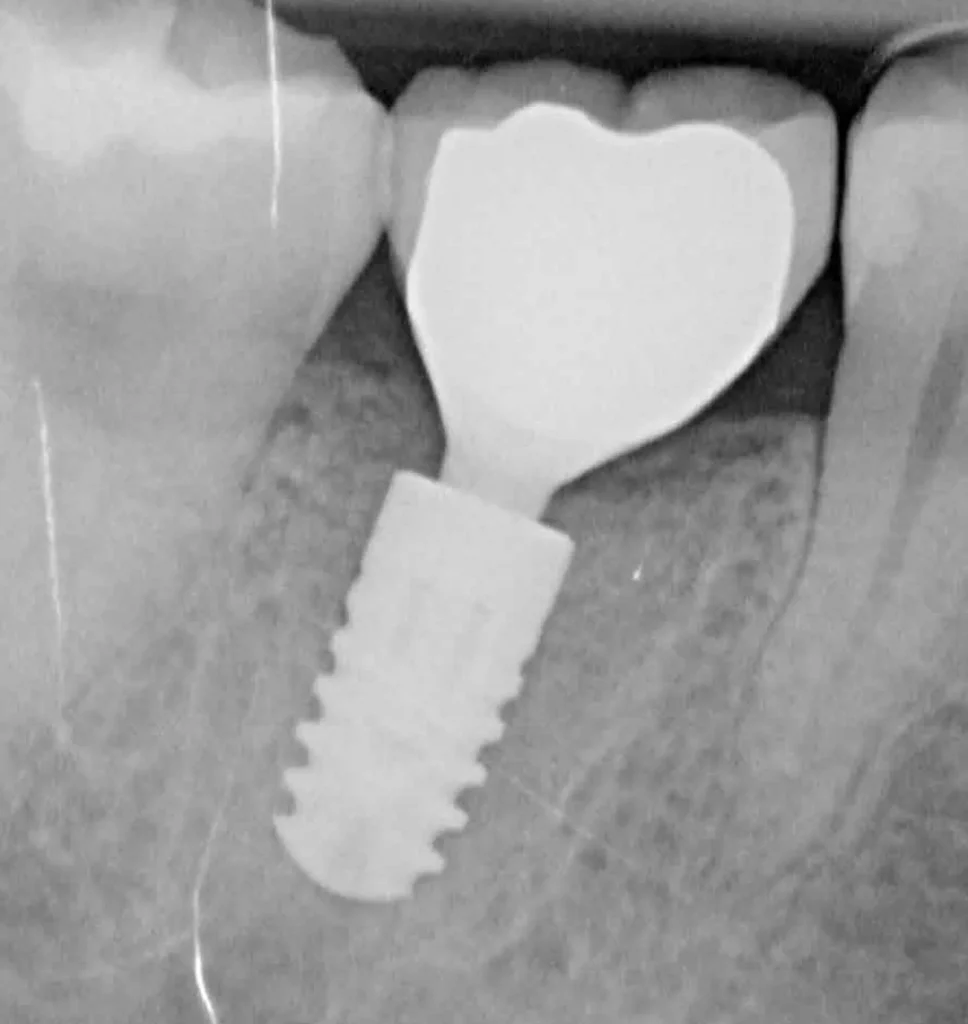

This woman had a badly broken down lower molar that had split apart and had been painfully abscessing for months. Unfortunately, it was beyond saving, and it was extracted. Keen to have the space restored, the patient opted to have an implant placed.

Below shows the crown fitted on to the implant post.